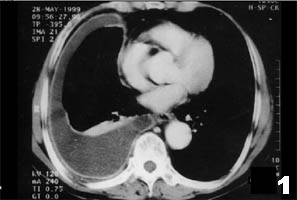

2.其他真菌性變應性呼吸道疾病真菌除可以誘發變應性哮喘外,還可誘發其他肺實質的真菌性支氣管肺的變應性疾病,如真菌誘發的變應性肺炎(又稱真菌性外源性變應性肺泡炎)等,這是一組非IgE介導的真菌性變態反應在肺部的表現,其發病機制、病理生理和臨床過程均與支氣管哮喘有較大區別。作為哮喘防治工作者對這疾病也應有所了解,以便於臨床工作中鑑別診斷和治療。

這些病人常由於吸入生活或職業環境中的各種真菌孢子而致病。有些非真菌性的無機或有機粉塵,化學或藥物等顆粒,吸入後也可致病,但真菌為其主要的病原。該類疾病在臨床上可分為兩類。一類為速髮型,稱急性過敏性肺炎,症狀為在大量吸入致敏真菌後4~8h內出現畏寒、發熱、咳嗽、咳痰、喘憋、乏力、頭痛、肺底有濕性囉音、末梢血白細胞增高等。重者可有肺組織浸潤性病變,肺功能可出現通氣功能不足。二類為隱匿型,亦稱亞急性或慢性過敏性肺炎,是由於長期吸入某種真菌孢子,短期內不出現症狀,日久逐漸出現咳嗽、氣促、乏力、消瘦、活動後氣喘明顯,肺底濕囉音,可有杵狀指,胸部X線出現肺紋理增多,晚期廣泛肺纖維化。肺功能為限制性通氣功能不足,肺組織出現不可逆病變,預後不好。